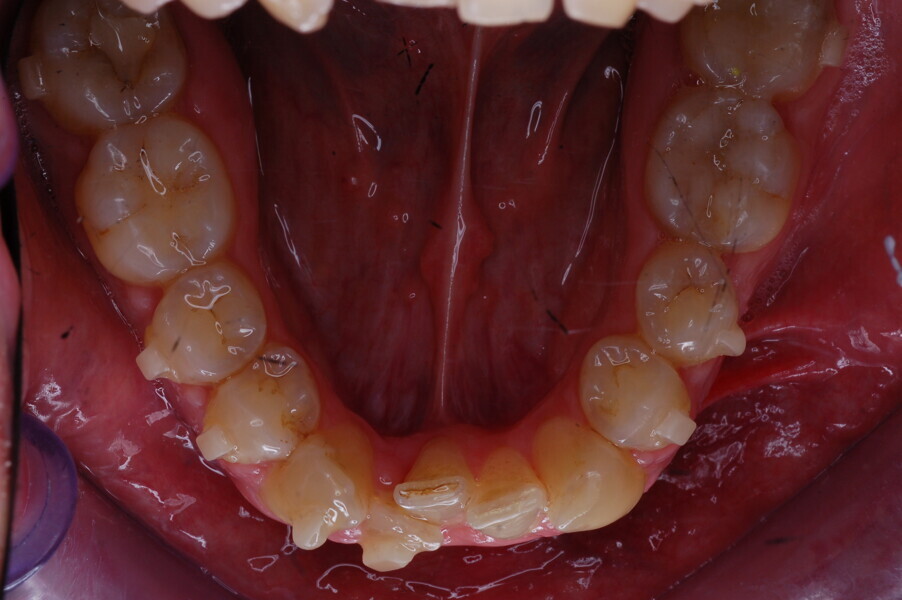

A healthy 39-year-old man presented to our orthodontic office with the chief complaint of an unattractive dental appearance and fear of the orthognathic surgery proposed by another orthodontist. Clinically, the patient’s profile was straight, and the frontal view did not show any facial asymmetry. The functional examination did not reveal any mandibular deviation or reduced movements. The patient had no joint pain, and no joint noise was observed.

Figs. 1–8: Pretreatment facial and intra-oral photographs.

From the periodontal point of view, the patient showed a good attitude to oral hygiene, but crowding of the mandibular incisors made cleaning difficult in that area, causing plaque accumulation and localised gingival inflammation. The panoramic radiograph revealed the presence of the mandibular third molars and confirmed the absence of the mandibular right central incisor (Fig. 10).

The cephalometric analysis showed a skeletal Class II malocclusion (convexity of Point A: 4.9 mm), a slightly retruded chin position (facial depth: 78.1°) and a skeletal open bite tendency (lower facial height: 53.19°; facial axis: 80.58°; Fig. 9). The mandibular incisors were lingually tipped (Li–APog: 9.3°) and retruded (Li–APog: 1.55 mm), and there was an increased inter-incisal angle of 142.9°.